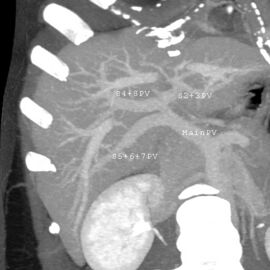

في نظام كوينو المستخدم على نطاق واسع، تُقسم الفصوص الوظيفية إلى إجمالي ثمانية أجزاء فرعية بناءً على المستوى العرضي من خلال تشعب الوريد البابي الرئيسي.[29] الفص المذنب هو بنية منفصلة تتلقى تدفق الدم من الفروع الوعائية اليمنى واليسرى.[30][31] يقسم تصنيف كوينو الكبد إلى ثمانية أجزاء كبدية مستقلة وظيفياً. كل جزء له تدفق وعائي داخلي وخارجي وتصريف صفراوي خاص به. في وسط كل جزء توجد فروع من الوريد البابي والشريان الكبدي والقناة الصفراوية. في محيط كل جزء يوجد تدفق وعائي خارجي عبر الأوردة الكبدية.[32] يستخدم نظام التصنيف الإمداد الوعائي في الكبد لفصل الوحدات الوظيفية (المرقمة من I إلى VIII) مع الوحدة 1، الفص المذنب، الذي يتلقى إمداده من كل من الفرعين الأيمن والأيسر للوريد البابي. يحتوي على واحد أو أكثر من الأوردة الكبدية التي تصب مباشرة في الوريد الأجوف السفلي.[29] يتم ترقيم بقية الوحدات (II إلى VIII) بطريقة عقارب الساعة:[32]

صورة مقطعية محورية تظهر أوردة كبدية شاذة تنتشر على السطح الأمامي تحت المحفظة للكبد.[73]